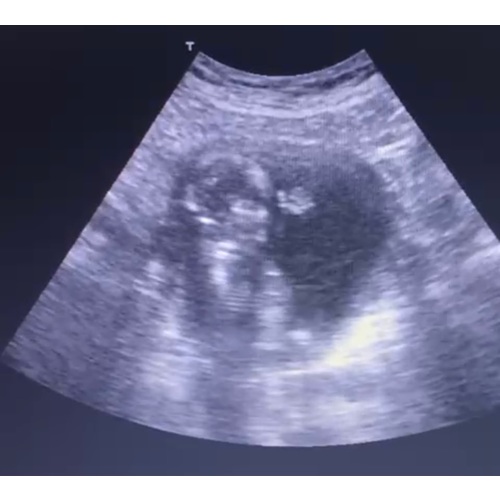

Mooie echo! Dat handje! ☺️